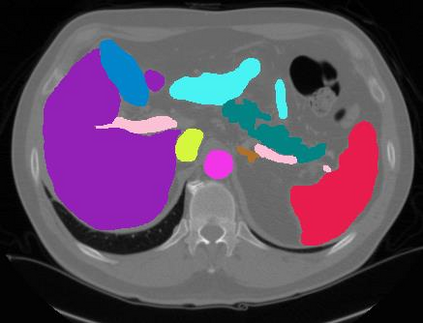

Vision transformers, with their ability to more efficiently model long-range context, have demonstrated impressive accuracy gains in several computer vision and medical image analysis tasks including segmentation. However, such methods need large labeled datasets for training, which is hard to obtain for medical image analysis. Self-supervised learning (SSL) has demonstrated success in medical image segmentation using convolutional networks. In this work, we developed a \underline{s}elf-distillation learning with \underline{m}asked \underline{i}mage modeling method to perform SSL for vision \underline{t}ransformers (SMIT) applied to 3D multi-organ segmentation from CT and MRI. Our contribution is a dense pixel-wise regression within masked patches called masked image prediction, which we combined with masked patch token distillation as pretext task to pre-train vision transformers. We show our approach is more accurate and requires fewer fine tuning datasets than other pretext tasks. Unlike prior medical image methods, which typically used image sets arising from disease sites and imaging modalities corresponding to the target tasks, we used 3,643 CT scans (602,708 images) arising from head and neck, lung, and kidney cancers as well as COVID-19 for pre-training and applied it to abdominal organs segmentation from MRI pancreatic cancer patients as well as publicly available 13 different abdominal organs segmentation from CT. Our method showed clear accuracy improvement (average DSC of 0.875 from MRI and 0.878 from CT) with reduced requirement for fine-tuning datasets over commonly used pretext tasks. Extensive comparisons against multiple current SSL methods were done. Code will be made available upon acceptance for publication.